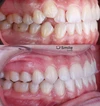

Diş Çapraşıklığı